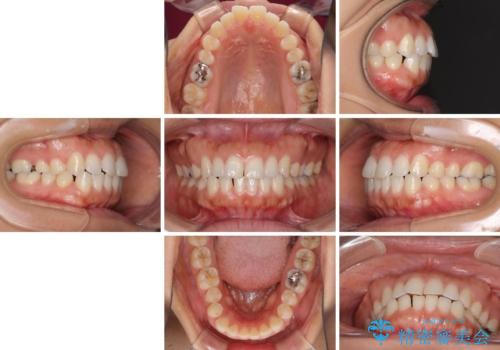

- 前歯の隙間と口元の突出感を気にして来院された患者様です。

嚥下時に舌を突出させる癖があり、成長期に下顎が有意に成長し、歯と歯の間に隙間ができてしまいました。

舌の癖を改善し、インビザラインにて治療を行うこととしました。